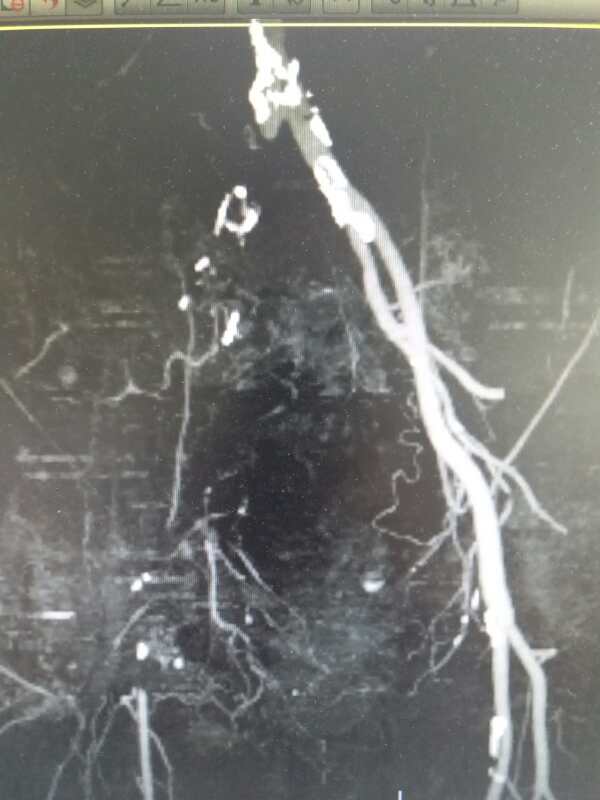

54岁男性,右足疼痛半月余。患者半月前无明显诱因突发右下肢疼痛,行走后加重,休息减轻。超声提示腹主动脉左髂动脉多发狭窄闭塞,右髂动静脉闭塞。CTA

对比正常解剖模式图,我们可以发现:右侧髂总髂内髂外股总动脉未显影,股深动脉未显影,右侧股浅动脉起始段未见显影,考虑有血栓闭塞的可能。